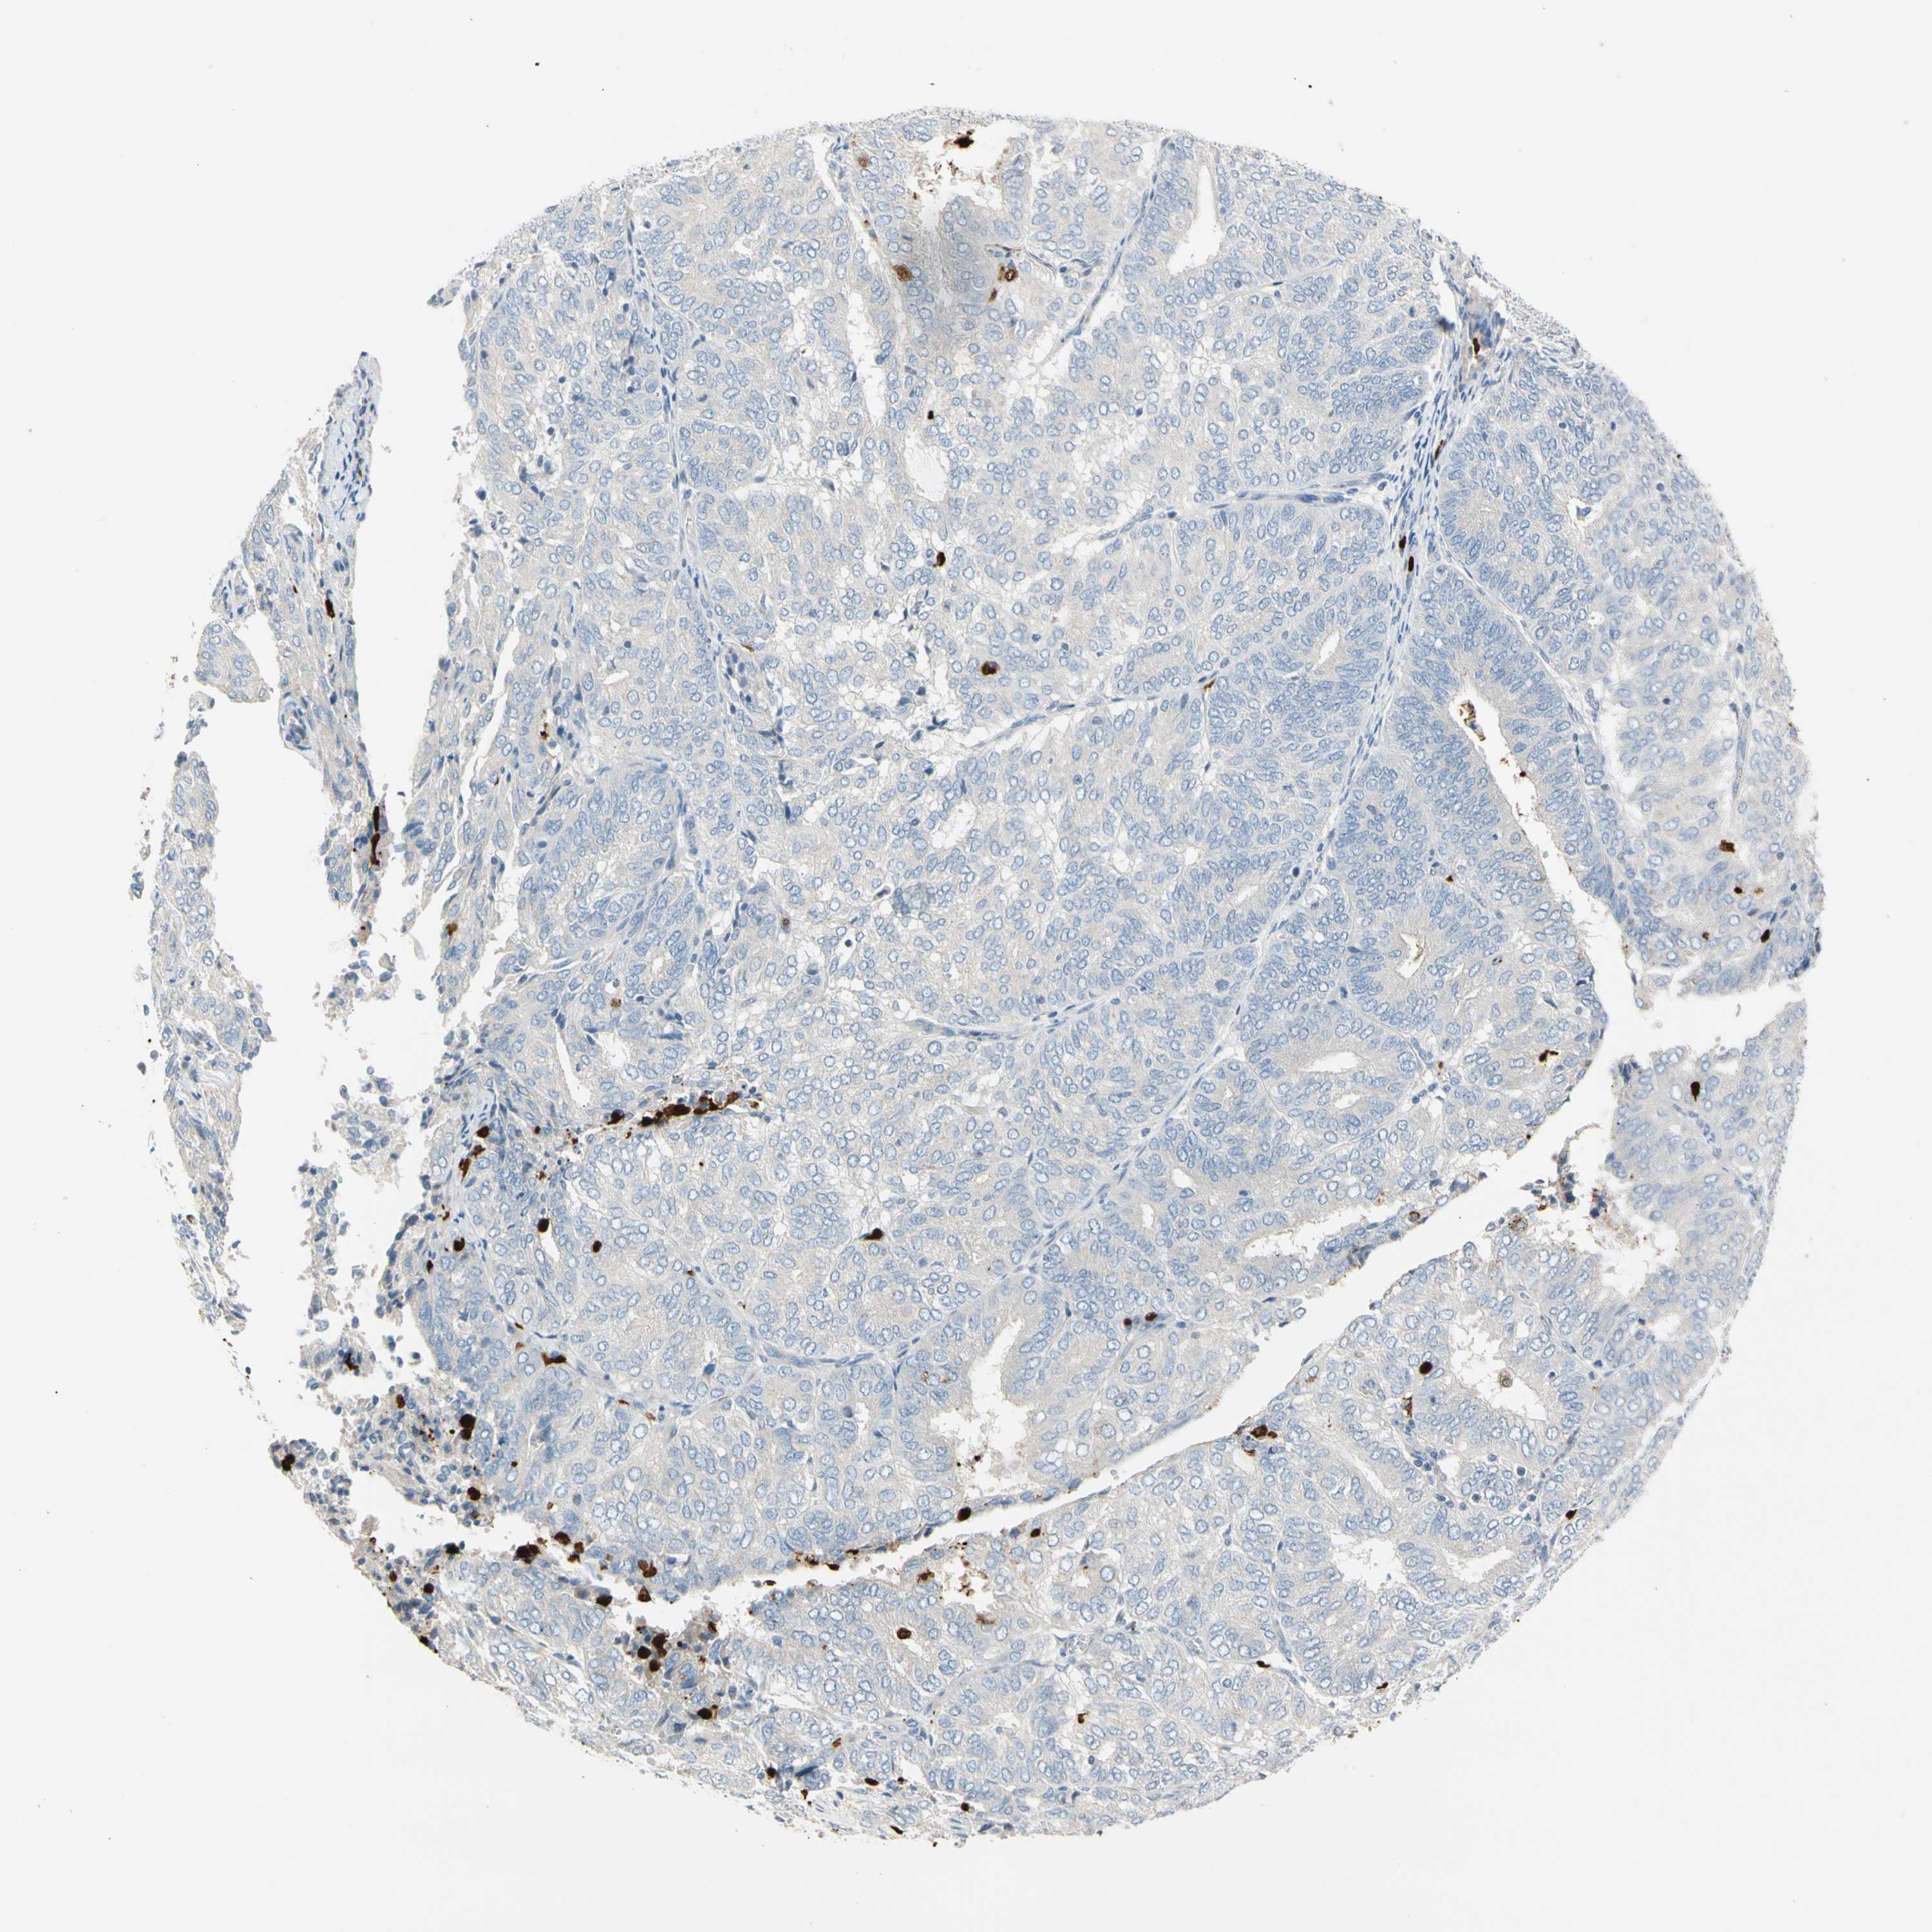

ENDOMETRIAL CANCER - Protein expressioni

A mouse-over function shows sample information and annotation data. Click on an image to view it in a full screen mode. Samples can be filtered based on level of antibody staining by selecting one or several of the following categories: high, medium, low and not detected. The assay and annotation is described here.

Note that samples used for immunohistochemistry by the Human Protein Atlas do not correspond to samples in the TCGA dataset.

Antibody stainingi

Antibody staining in the annotated cell types in the current human tissue is reported as not detected, low, medium, or high, based on conventional immunohistochemistry profiling in selected tissues. This score is based on the combination of the staining intensity and fraction of stained cells.

Each image is clickable and will lead to virtual microscopy that enables deeper exploration of all samples and also displays staining intensity scores, fraction scores and subcellular localization as well as patient and tissue information for each sample.

Antibody HPA008052

Antibody CAB010277

Staining

High

Medium

Low

Not detected

Intensity

Strong

Moderate

Weak

Negative

Quantity

>75%

75%-25%

<25%

None

Location

Nuclear

Cytoplasmic/membranous

Cytoplasmic/membranous,nuclear

Adenocarcinoma, NOS